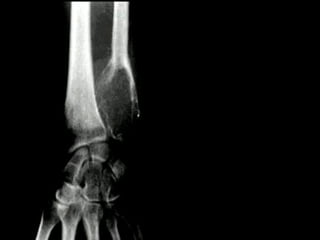

La osteomielitis es una infección súbita o de larga data del hueso o médula

ósea, normalmente causada por una bacteria piógena o micobacteria y

hongos. Los factores de riesgo son trauma reciente, diabetes, hemodiálisis y

drogadicción intravenosa.

La Osteomielitis se define como una inflamación extensa del hueso,

implicando a toda porción esponjosa, medular, cortical, periostio, vasos

sanguíneos, nervios y epífisis. La inflamación puede ser aguda, subaguda o

crónica y presenta un desarrollo clínico diferente según su naturaleza (1-5).

En el caso de los maxilares se considera la infección odontógena como la

causa más frecuente de osteomielitis. Se puede presentar a cualquier edad

con un predominio entre los hombres. Afecta principalmente al maxilar

inferior. En el maxilar superior es más raro, debido a una mayor

vascularización .